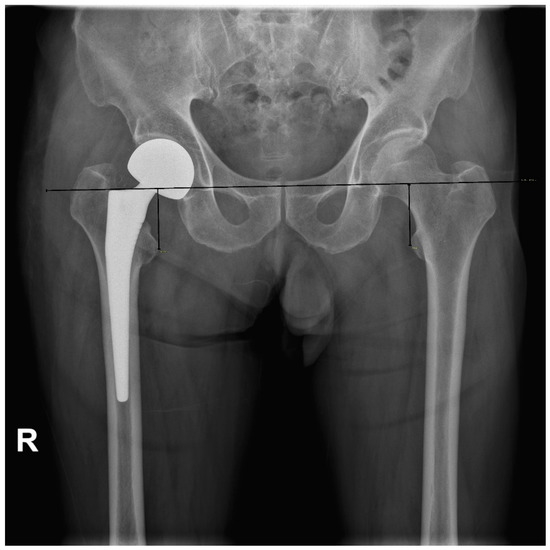

| Gonzalez et al. (2005) [16] | 1.71 | Measuring between the proximal edge of the lesser trochanter and the center of rotation of the femoral head (HLD) |

| Lim et al. (2013) [18] | 1.5 | Measuring head to lesser trochanter length using PACS and reproducing it in the operative field with a modular neck system |